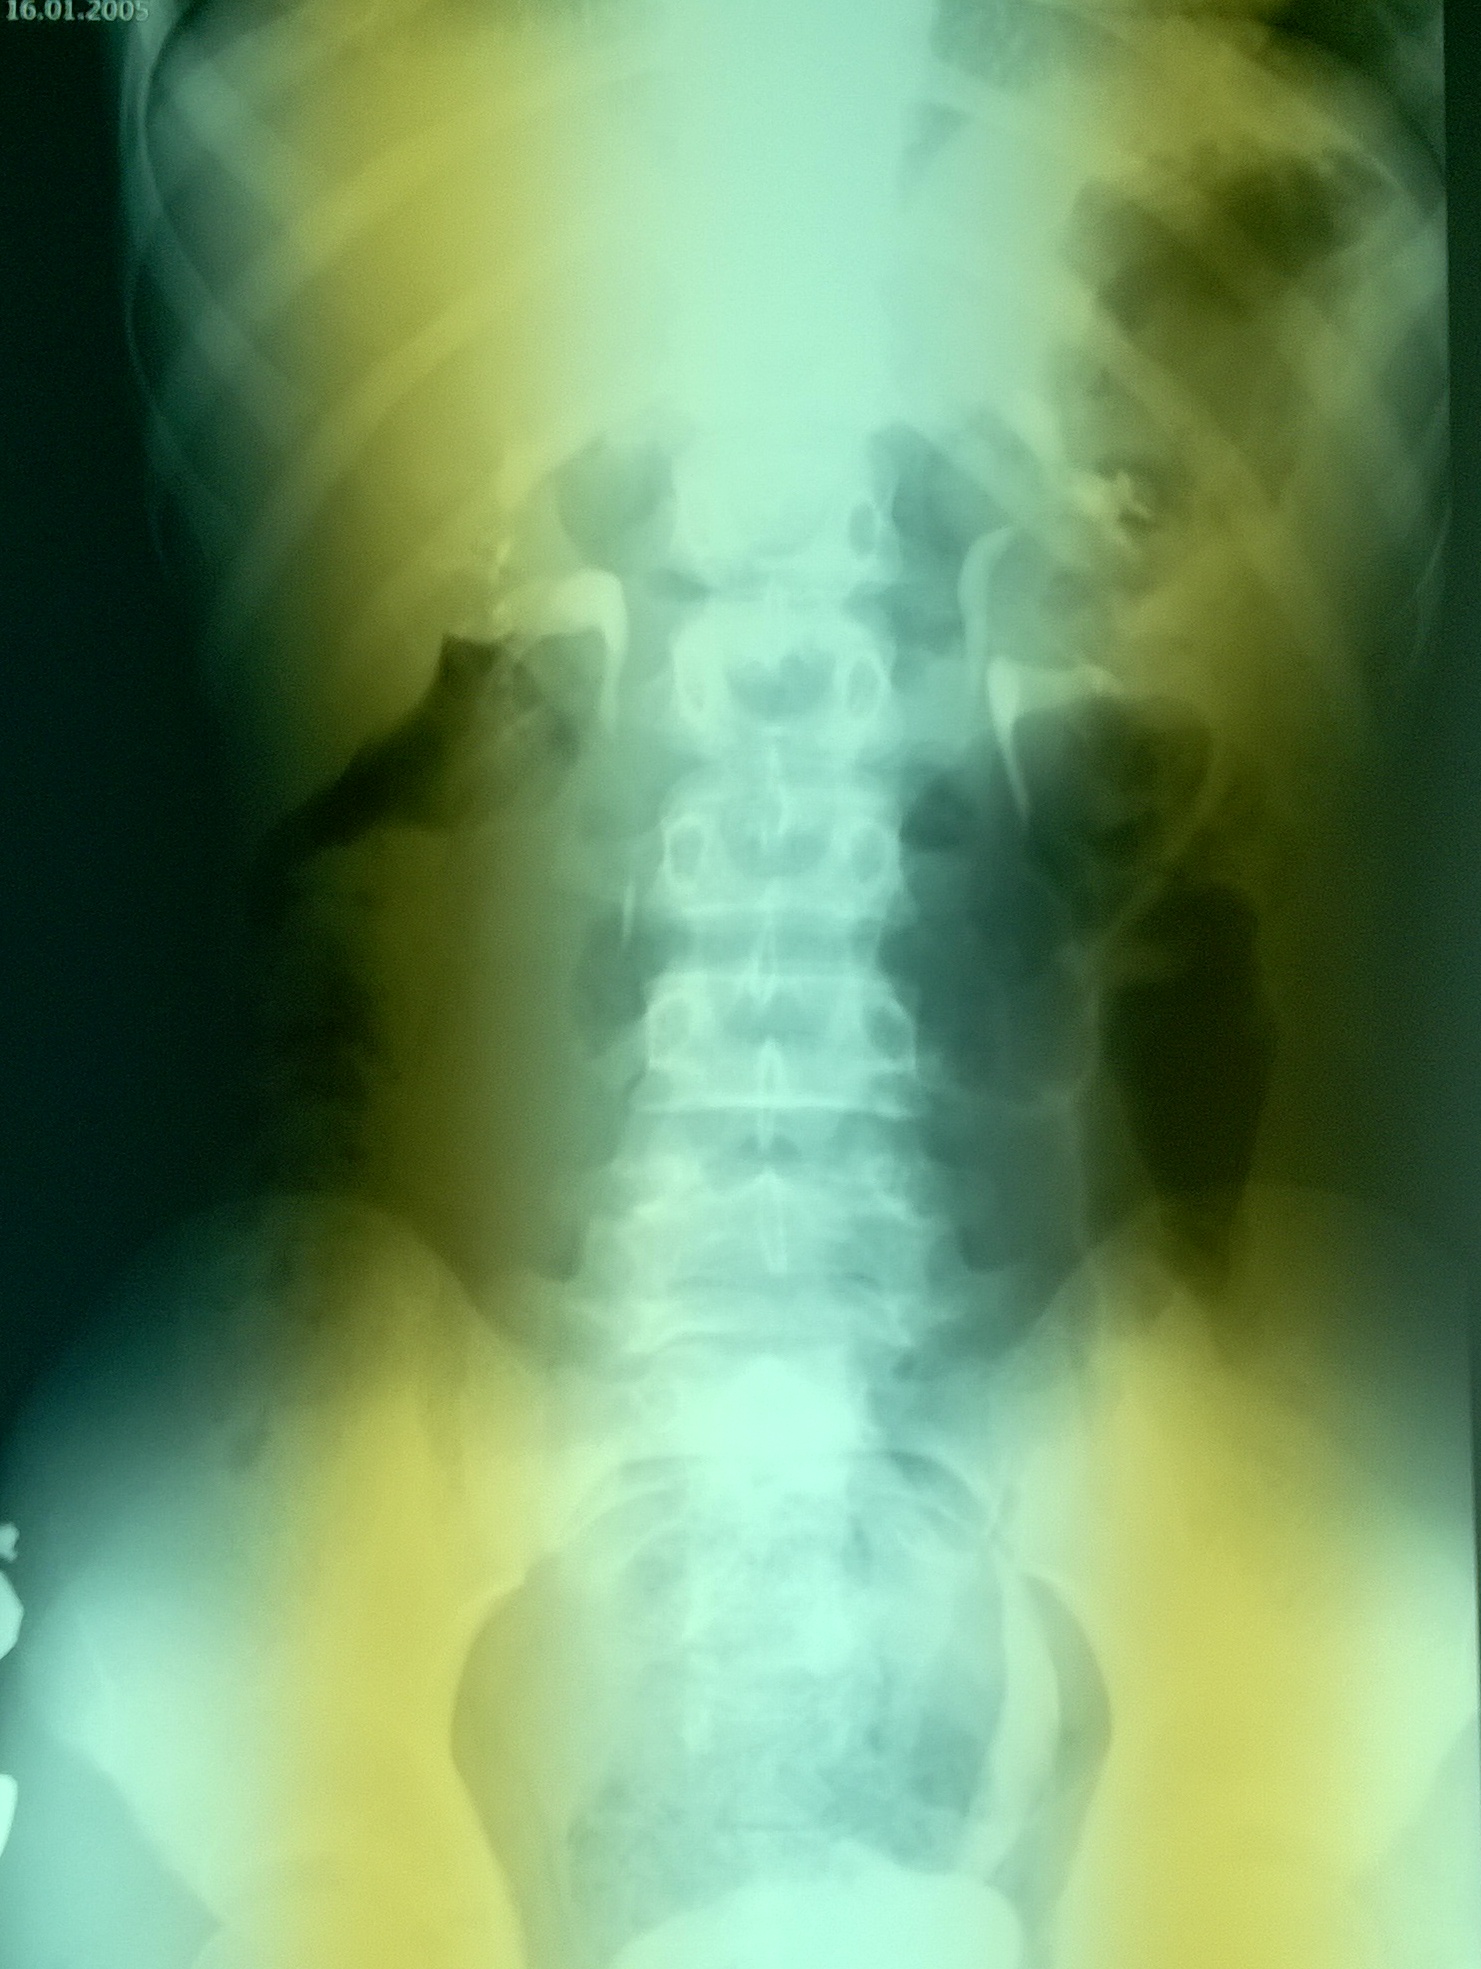

На Ro обследовании удвоение подтвердилось.

экскреторная урография